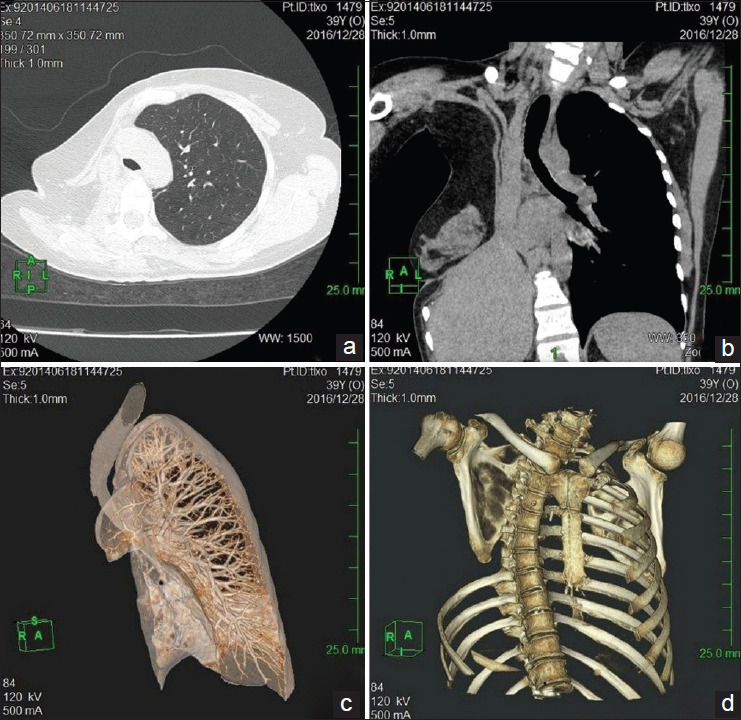

A 39-year-old female has postoperative empyema with bronchial stump fistula (BSF) after pneumonectomy due to ineffective tuberculosis chemotherapy. Transpleural reamputation of the right main bronchial stump with simultaneous 8-rib thoracoplasty, 6 attempts at endobronchial valve implantation and thoracostomy have failed to cure BSF and empyema. Consequently, an alternative treatment-transsternal transpericardial wedge-shaped resection of the tracheal bifurcation was performed despite its difficulty and was successful. This clinical case demonstrates the complications of BSF with tuberculosis empyema treatment in spite of there existing many alternative therapies. The need for new more effective treatments is highlighted, as well as safe and less technically difficult interventions which could assist patients with BSF.

Abstract Image